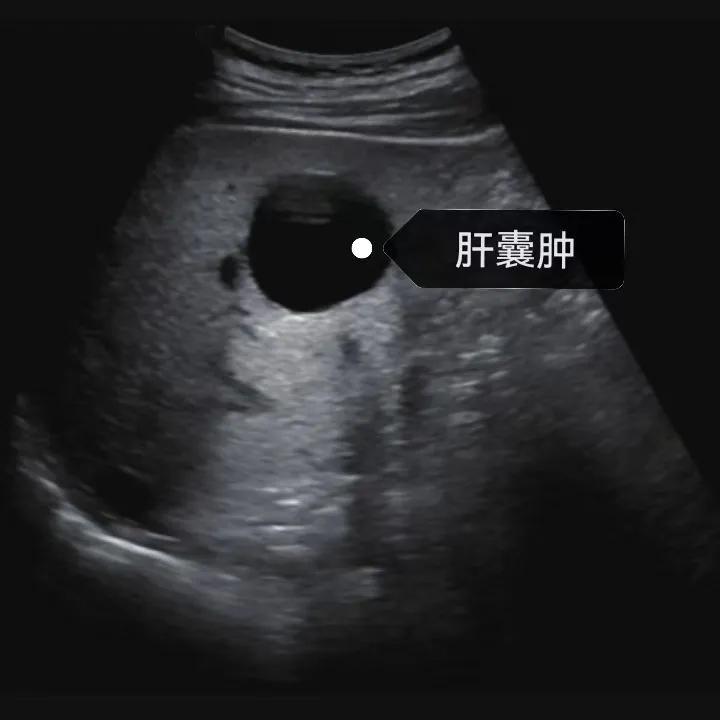

肝囊腫是一種常見的肝臟良性疾病,呈圓形或橢圓形,外由上皮細(xì)胞包裹形成包膜,內(nèi)由清亮、無色、無細(xì)胞成分的囊液填充,看上去就像是一顆注滿了水的氣球,因此通俗一點說就是肝臟中的“水泡”。

超聲通常是診斷肝囊腫的首選方法,彩超對肝囊腫的檢出率可達98%,<1cm的囊腫也可檢出。肝囊腫常表現(xiàn)為圓形或橢圓形無回聲,包膜光滑完整,邊界清晰,可有側(cè)壁回聲失落征象,后方回聲增強。病程長、囊腫較大者或囊內(nèi)有過出血、感染者,無回聲腔內(nèi)可見少量絮狀回聲漂浮。超聲對肝囊腫的診斷準(zhǔn)確而靈敏,且方法簡單、無創(chuàng)、費用低、可重復(fù)性高,因此常常被作為首選。